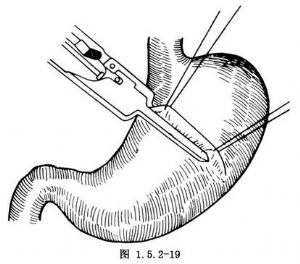

进腹后,显露出胃体部,于胃窦部大弯侧游离切断胃网膜右动脉,沿胃大弯游离胃结肠韧带,保留胃网膜血管,于胃体部大弯及小弯侧各缝一针牵引线将胃前壁提起。用侧-侧吻合器夹住被提起的胃前壁5~6cm,由小弯向大弯的方向夹紧后,推动推杆完成缝合及切开(图1.5.2-19)。